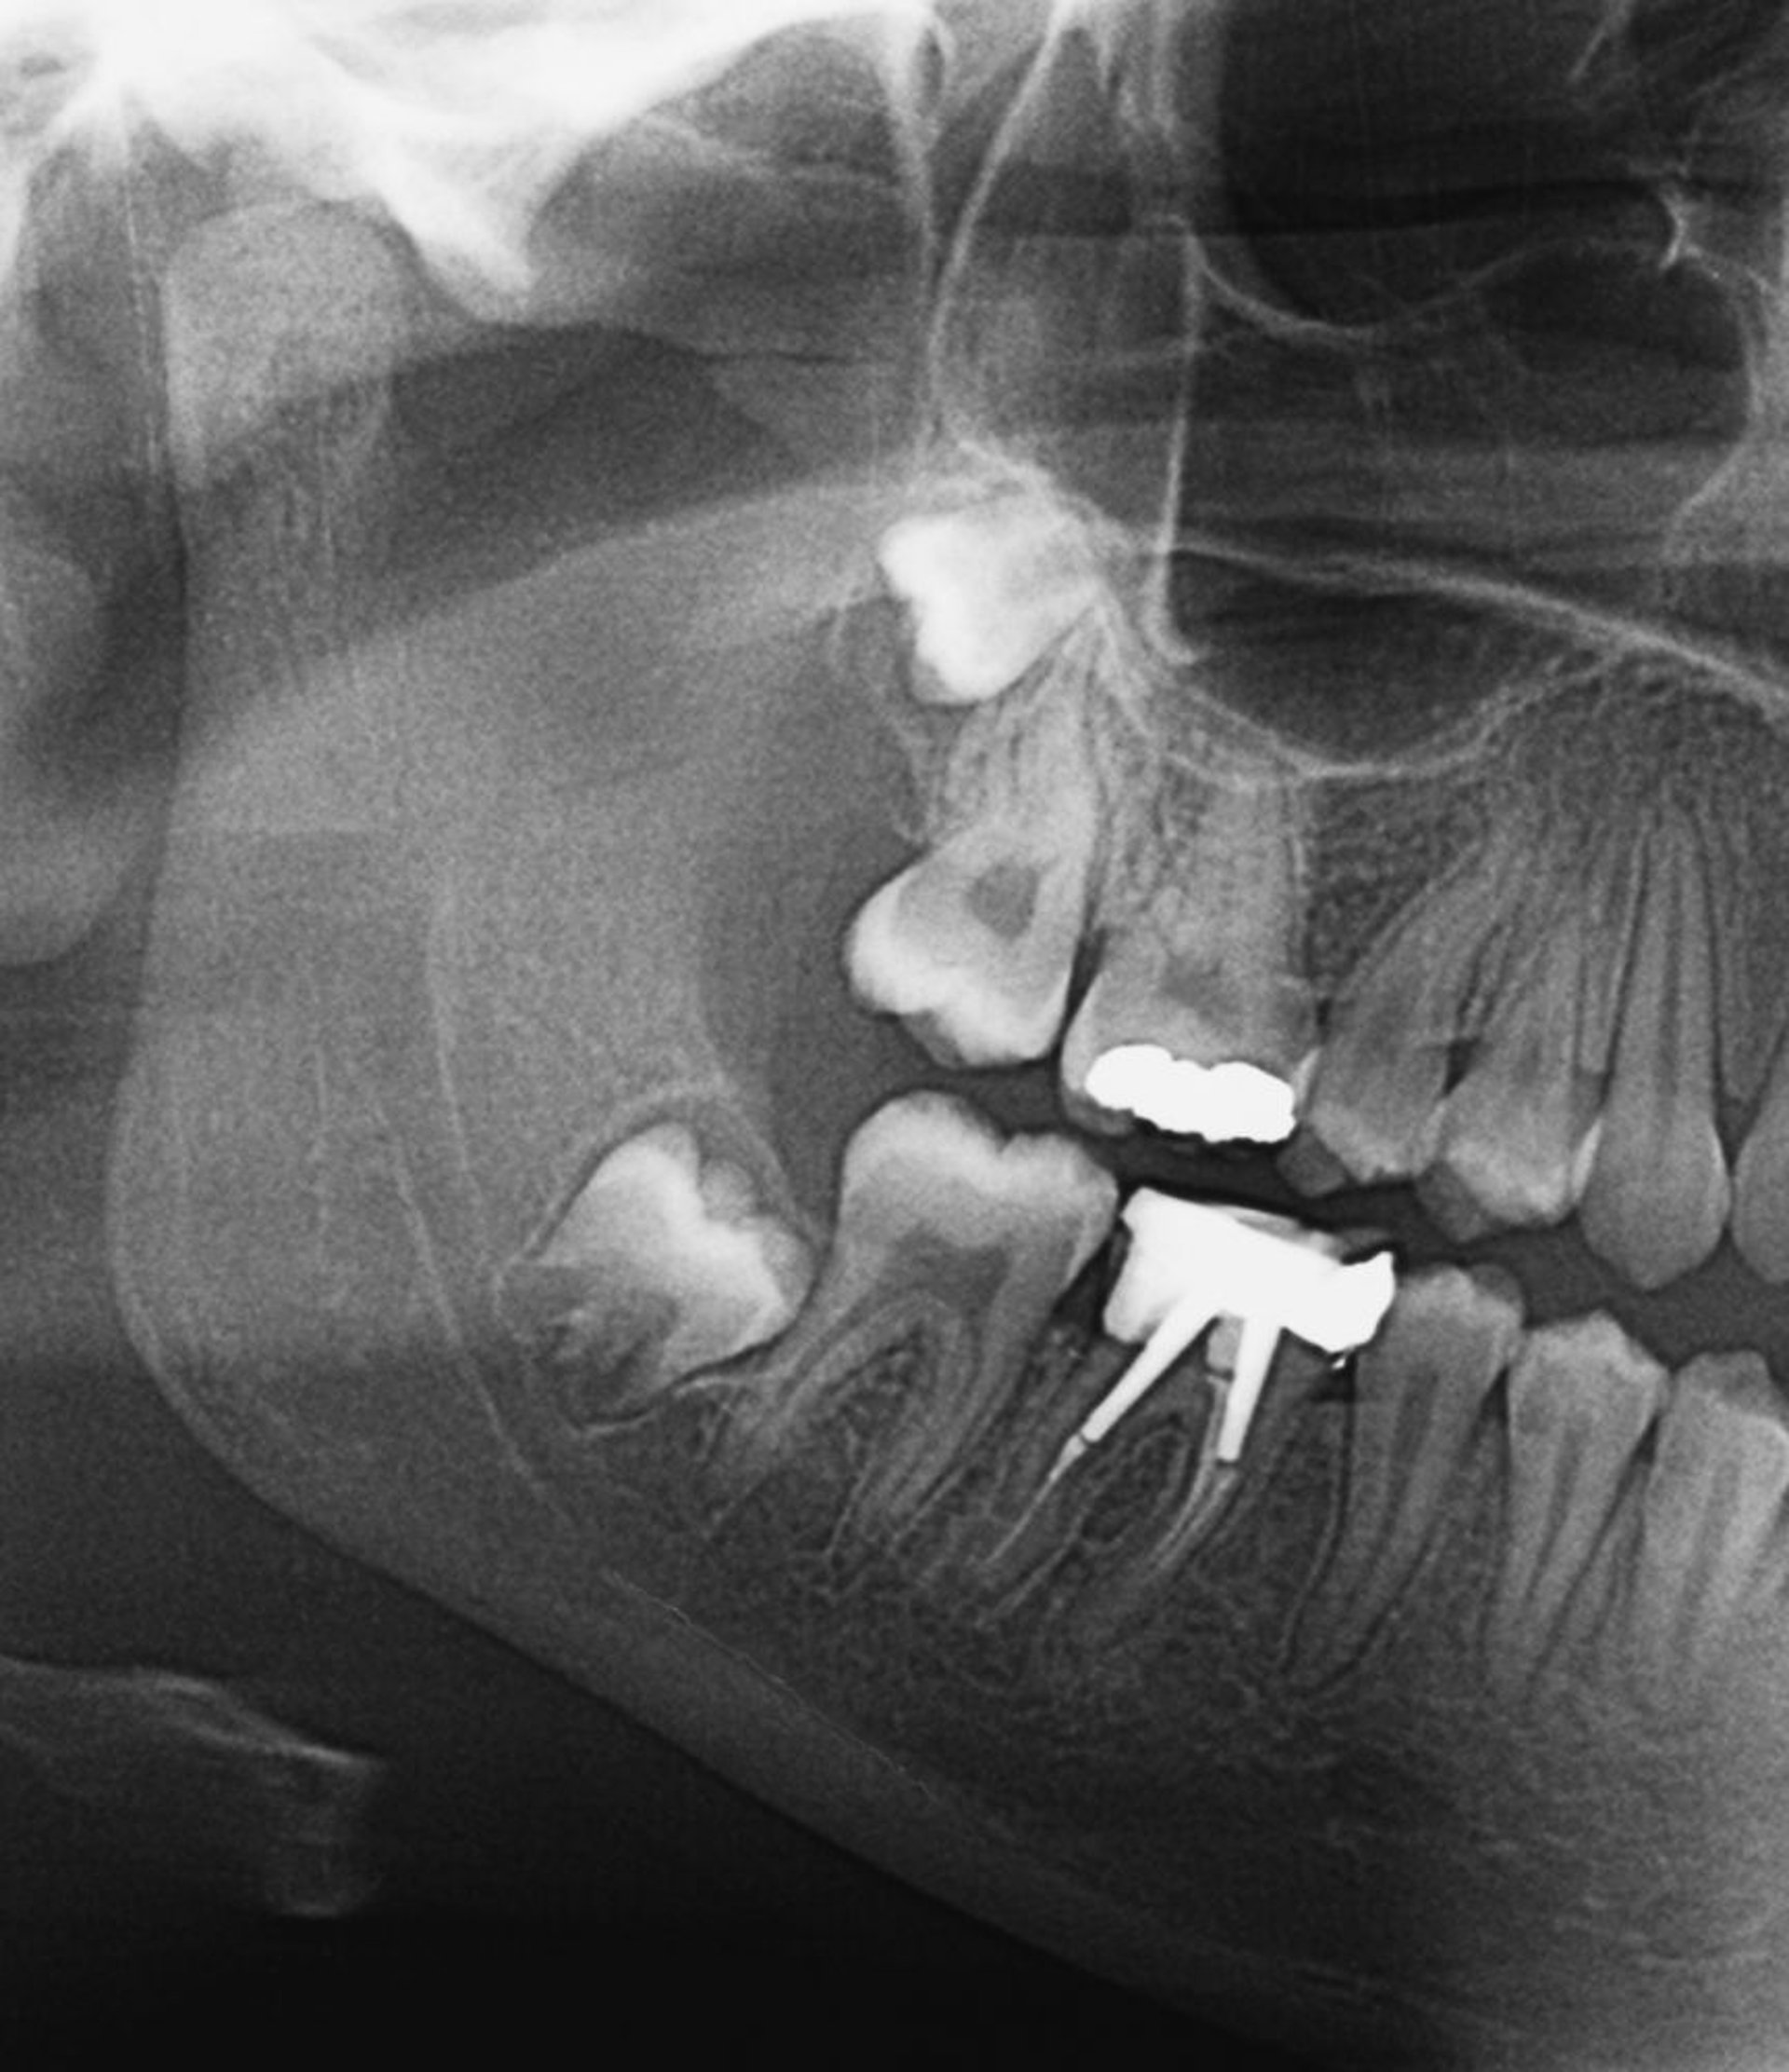

Dents de sagesse incluses

Cette radiographie montre des dents de sagesse incluses. Lorsque les dents de sagesse sortent ou si elles sont partiellement incluses, une péricoronarite peut se développer.

ZEPHYR/SCIENCE PHOTO LIBRARY